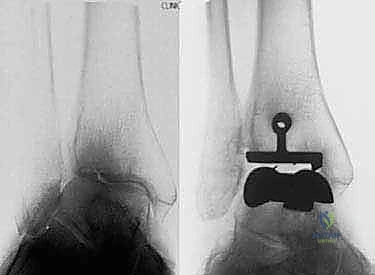

- الأشعة السينية (X-rays) بوضعية الوقوف: وهي الأداة الذهبية للتشخيص. صور الأشعة والوزن محمل على القدم (Weight-bearing X-rays) تظهر بدقة مدى تآكل الغضروف (ضيق المسافة المفصلية)، وجود نتوءات عظمية (Osteophytes)، وأي انحراف في المحور الميكانيكي للساق.

1. نظام سالتو لمفصل الكاحل الكلي (Salto Total Ankle Prosthesis - Mobile Bearing)

مفصل سالتو الأصلي هو ثمرة أبحاث أوروبية مكثفة. تم تطويره بين عامي 1994 و 1996، وبدأ استخدامه السريري بنجاح باهر في يناير 1997.

* التصميم الميكانيكي: يُعرف بأنه نظام ذو "مكون متحرك" (Mobile-bearing). يتكون من ثلاثة أجزاء رئيسية:

1. مكون معدني يثبت في أسفل عظمة الساق (Tibia).

2. مكون معدني يثبت في أعلى عظمة الكاحل (Talus).

3. قطعة بلاستيكية من البولي إيثيلين عالي الكثافة (Polyethylene insert): هذه القطعة ليست ثابتة، بل تنزلق بحرية بين المكونين المعدنيين.

* الميزة الكبرى: هذا التصميم يسمح بـ "التموضع الذاتي" (Self-alignment). أثناء الحركة، تتحرك القطعة البلاستيكية لتتكيف مع القوى الميكانيكية، مما يقلل من الضغط الواقع على واجهة التثبيت بين المعدن والعظم، ويحاكي حركة الكاحل المعقدة بشكل رائع.

* التثبيت: هو مفصل "غير إسمنتي". يتم تغطية الأسطح المعدنية الملامسة للعظم بطبقة مسامية من التيتانيوم وهيدروكسي أباتيت (Hydroxyapatite). هذه الطبقة تشجع العظم الطبيعي للمريض على النمو داخل مسام المفصل (Bone Ingrowth)، مما يوفر تثبيتاً بيولوجياً صلباً يدوم لسنوات طويلة.

2. نظام سالتو تالاريس (Salto-Talaris Prosthesis - Fixed Bearing)

بناءً على النجاح الهائل لنظام سالتو، تم تطوير نظام سالتو تالاريس لتلبية متطلبات مدارس جراحية مختلفة (خاصة في الولايات المتحدة).

* التصميم الميكانيكي: يشارك هذا النظام نفس الهندسة التشريحية الممتازة للمكونات المعدنية لنظام سالتو، ولكن مع اختلاف جوهري واحد: المكون البلاستيكي (البولي إيثيلين) هنا ثابت (Fixed-bearing) ويتم قفله بإحكام داخل المكون المعدني العلوي (الظنبوبي).

* الفلسفة وراء التصميم: أثبتت الأبحاث وخبرة الجراحين، بما في ذلك الأستاذ الدكتور محمد هطيف، أنه إذا تم إجراء القصات العظمية أثناء الجراحة بدقة متناهية تتوافق مع التشريح الطبيعي، فإن الحاجة إلى حركة واسعة للمكون البلاستيكي تقل بشكل كبير.

* الميزة الكبرى: نظام سالتو تالاريس يوفر استقراراً